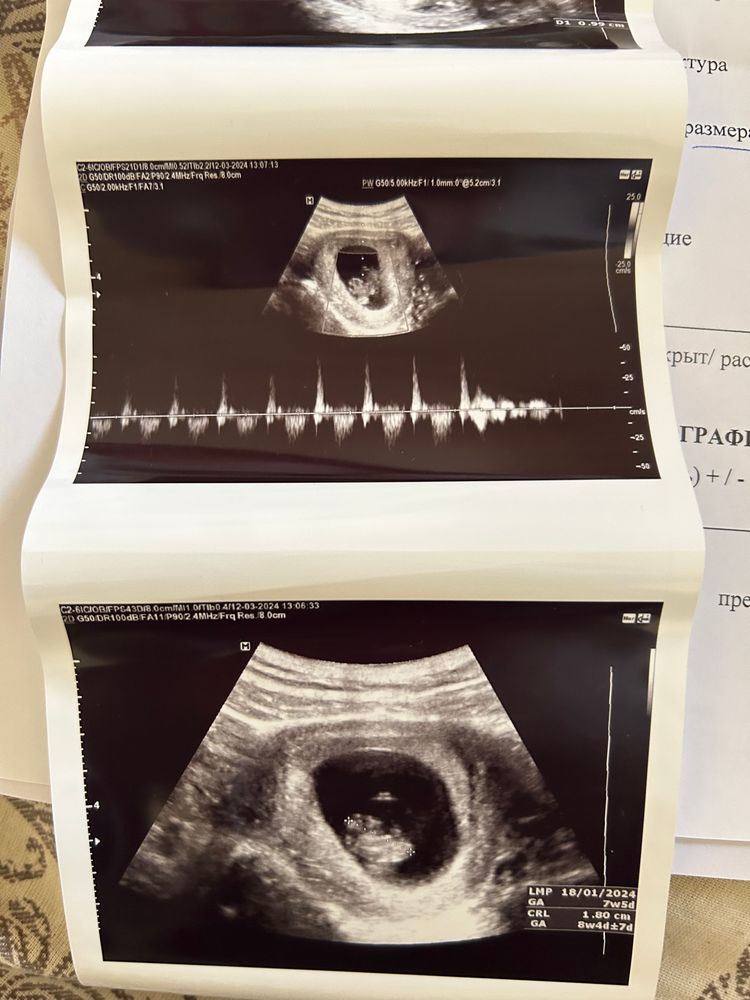

7 недель 5 дней💗

Послушали сердечко малыша🥰

По узи опережает на неделю, ставят 8 недель 5 дней, это не опасно, у кого было, подскажите пожалуйста?

и нашли маленькую гематому( откуда она могла взяться не понимаю..😪вроде работаю из дома удаленно, все хорошо должно быть, будем лечить